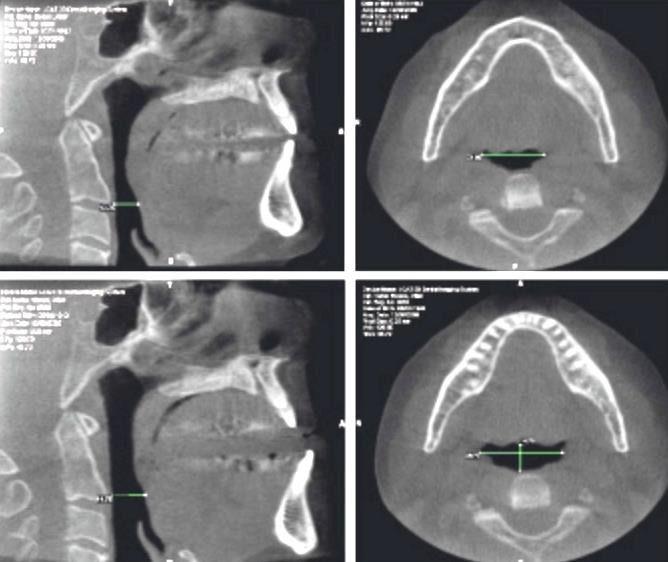

Maxillomandibular relationships can impact MAD selection

“Excessive” curve of Spee

Extension distal to the red line requires increase in vertical dimension (VD)

489